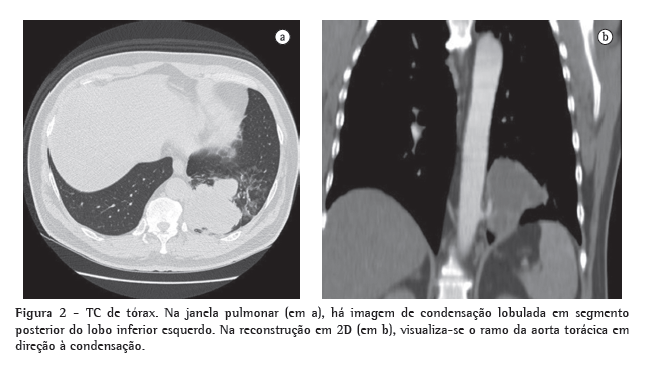

Ao exame, apresentava-se em bom estado geral, afebril, hemodinamicamente estável, com FC = 88 bpm e pressão arterial de 90-145 mmHg. A ausculta cardíaca era normal, e o exame pulmonar revelava expansibilidade e murmúrio vesicular diminuídos no terço inferior do hemitórax esquerdo, assim como macicez na percussão nesta região torácica. O restante do exame físico não revelava nenhuma anormalidade. Os exames laboratoriais de admissão, como hemograma, lipidograma, coagulograma, eletrólitos, função renal e hepática, eram normais. A VHS era de 32 mm/h. A sorologia para HIV foi negativa. A radiografia de tórax na internação demonstrava condensação no lobo inferior esquerdo no segmento posterior (Figura 1). Foi realizada TC do tórax com reconstrução em 2D, que demonstrava um ramo da aorta em direção à condensação pulmonar (Figura 2), compatível com o diagnóstico de sequestro pulmonar. O paciente foi encaminhado para cirurgia, tendo sido realizada lobectomia inferior esquerda para a ressecção do tecido pulmonar anômalo (Figura 3). Após a análise macroscópica da peça, caracterizou-se o sequestro intralobar. O paciente apresentou boa evolução pós-operatória, recebendo alta com acompanhamento ambulatorial.

Na investigação de um caso com suspeita de sequestro pulmonar, os exames de imagem têm dois objetivos principais: descartar a presença de outras patologias e caracterizar a presença do suprimento arterial anômalo.(12-15) A apresentação radiológica mais comum é de uma opacidade homogênea no segmento basal posterior do lobo inferior esquerdo. A arteriografia permite caracterizar as artérias anômalas, fornecendo informações valiosas no planejamento pré-operatório.(13) A TC helicoidal permite a visualização da origem e do curso dos vasos na maioria dos casos, assim como ocorre com a ressonância nuclear magnética. Nesses casos, é desnecessária a realização da angiografia.(10,15) O diagnóstico de sequestro pulmonar é caracterizado pela reconstrução na TC de tórax multicanal com contraste venoso, não sendo necessárias a aortografia e a ressonância ­magnética de tórax e abdômen, pois a TC de tórax e de andar superior do abdômen permite visualizar o vaso arterial de comunicação com sequestro e as alterações do parênquima pulmonar.(14,15)

Neste relato, o paciente referia dois episódios prévios de hemoptise de vulto na semana anterior e apresentava imagem hipotransparente retrocardíaca em base esquerda. O paciente não apresentava perda ponderal, e seu estado geral era preservado, dados que falavam contra uma etiologia neoplásica. O paciente não apresentava comorbidades prévias e negava história prévia de infecções de repetição. Foi internado para investigação diagnóstica. A TC de tórax com contraste endovenoso e reconstrução em 2D evidenciou a presença de sequestro pulmonar com individualização do suprimento arterial anômalo. O paciente foi submetido à cirurgia para a ressecção do tecido pulmonar anômalo e, após a análise macroscópica da peça, caracterizou-se o sequestro intralobar. O caso apresentado é raro, e o paciente apresentou boa evolução pós-operatória, recebendo alta com acompanhamento ambulatorial.